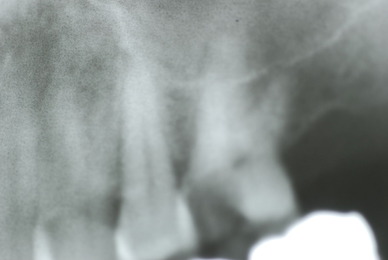

入れ歯の話から入りました。色々不満で注文があるようです。でも話が一段落して口腔内を調べると殆どの歯が重症で抜けそうな歯だらけなのです。

なぜ病気になるのかわからない方が多すぎます。歯が抜けるのは病気だからです。病気を治さずに何かお口の中に入れても土台である歯が抜けてしまっては同じことなのです。

何故歯が悪くなるのか、歯周病で抜けるのか分からなければ何を入れても歯は悪くなり抜けていくのです。